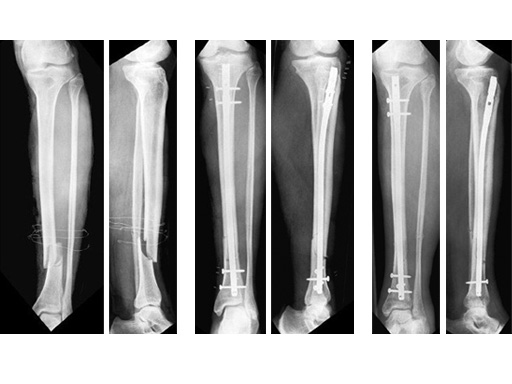

60-year-old man with a type II open 42-A2 fracture following a working accident.